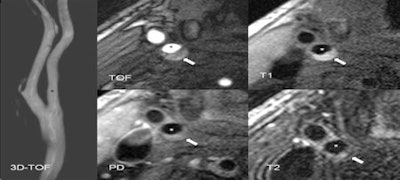

To find out, a high-resolution MRI examination of the carotid arteries is carried out within seven days of the stroke. After a year, this examination is repeated, and a brain MRI is performed. For black blood MRI, the signal from the blood flow is suppressed; the same sequences are in use for cardiac imaging. Dedicated surface coils are used; the so-called Blood Imaging Group in Munich, a team of graduate students, generates the necessary sequences for the study in the 3-tesla device. Imaging is done together with physicians and takes approximately 20-25 minutes for the carotids.

Based on this imaging method, type VI plaques can be identified. These plaques have a history of bleeding, clot formation, or rupture. One year after the launch of the study, data from the first 50 patients have now been evaluated to produce interim results.